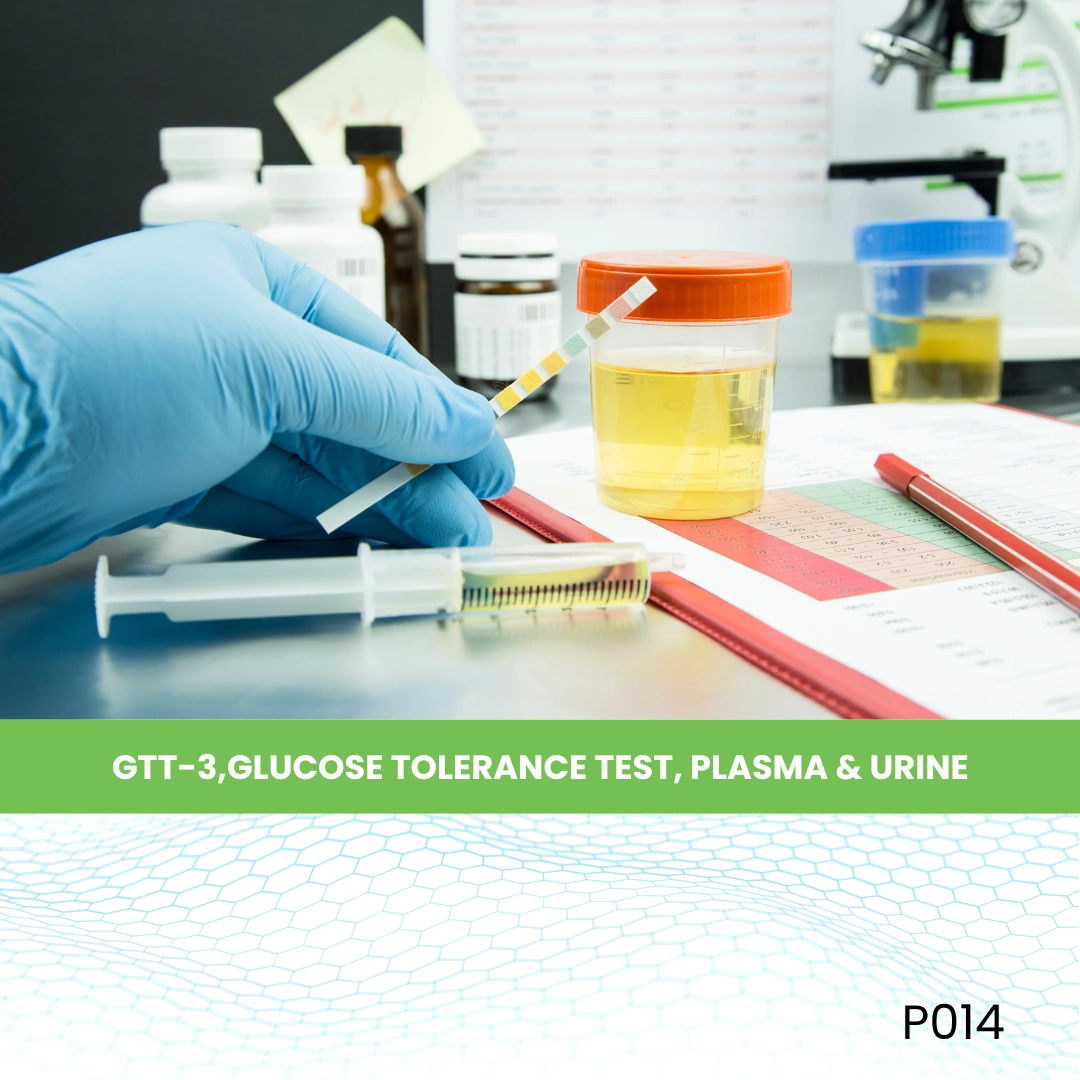

- Plasma Test

- Plasma Test